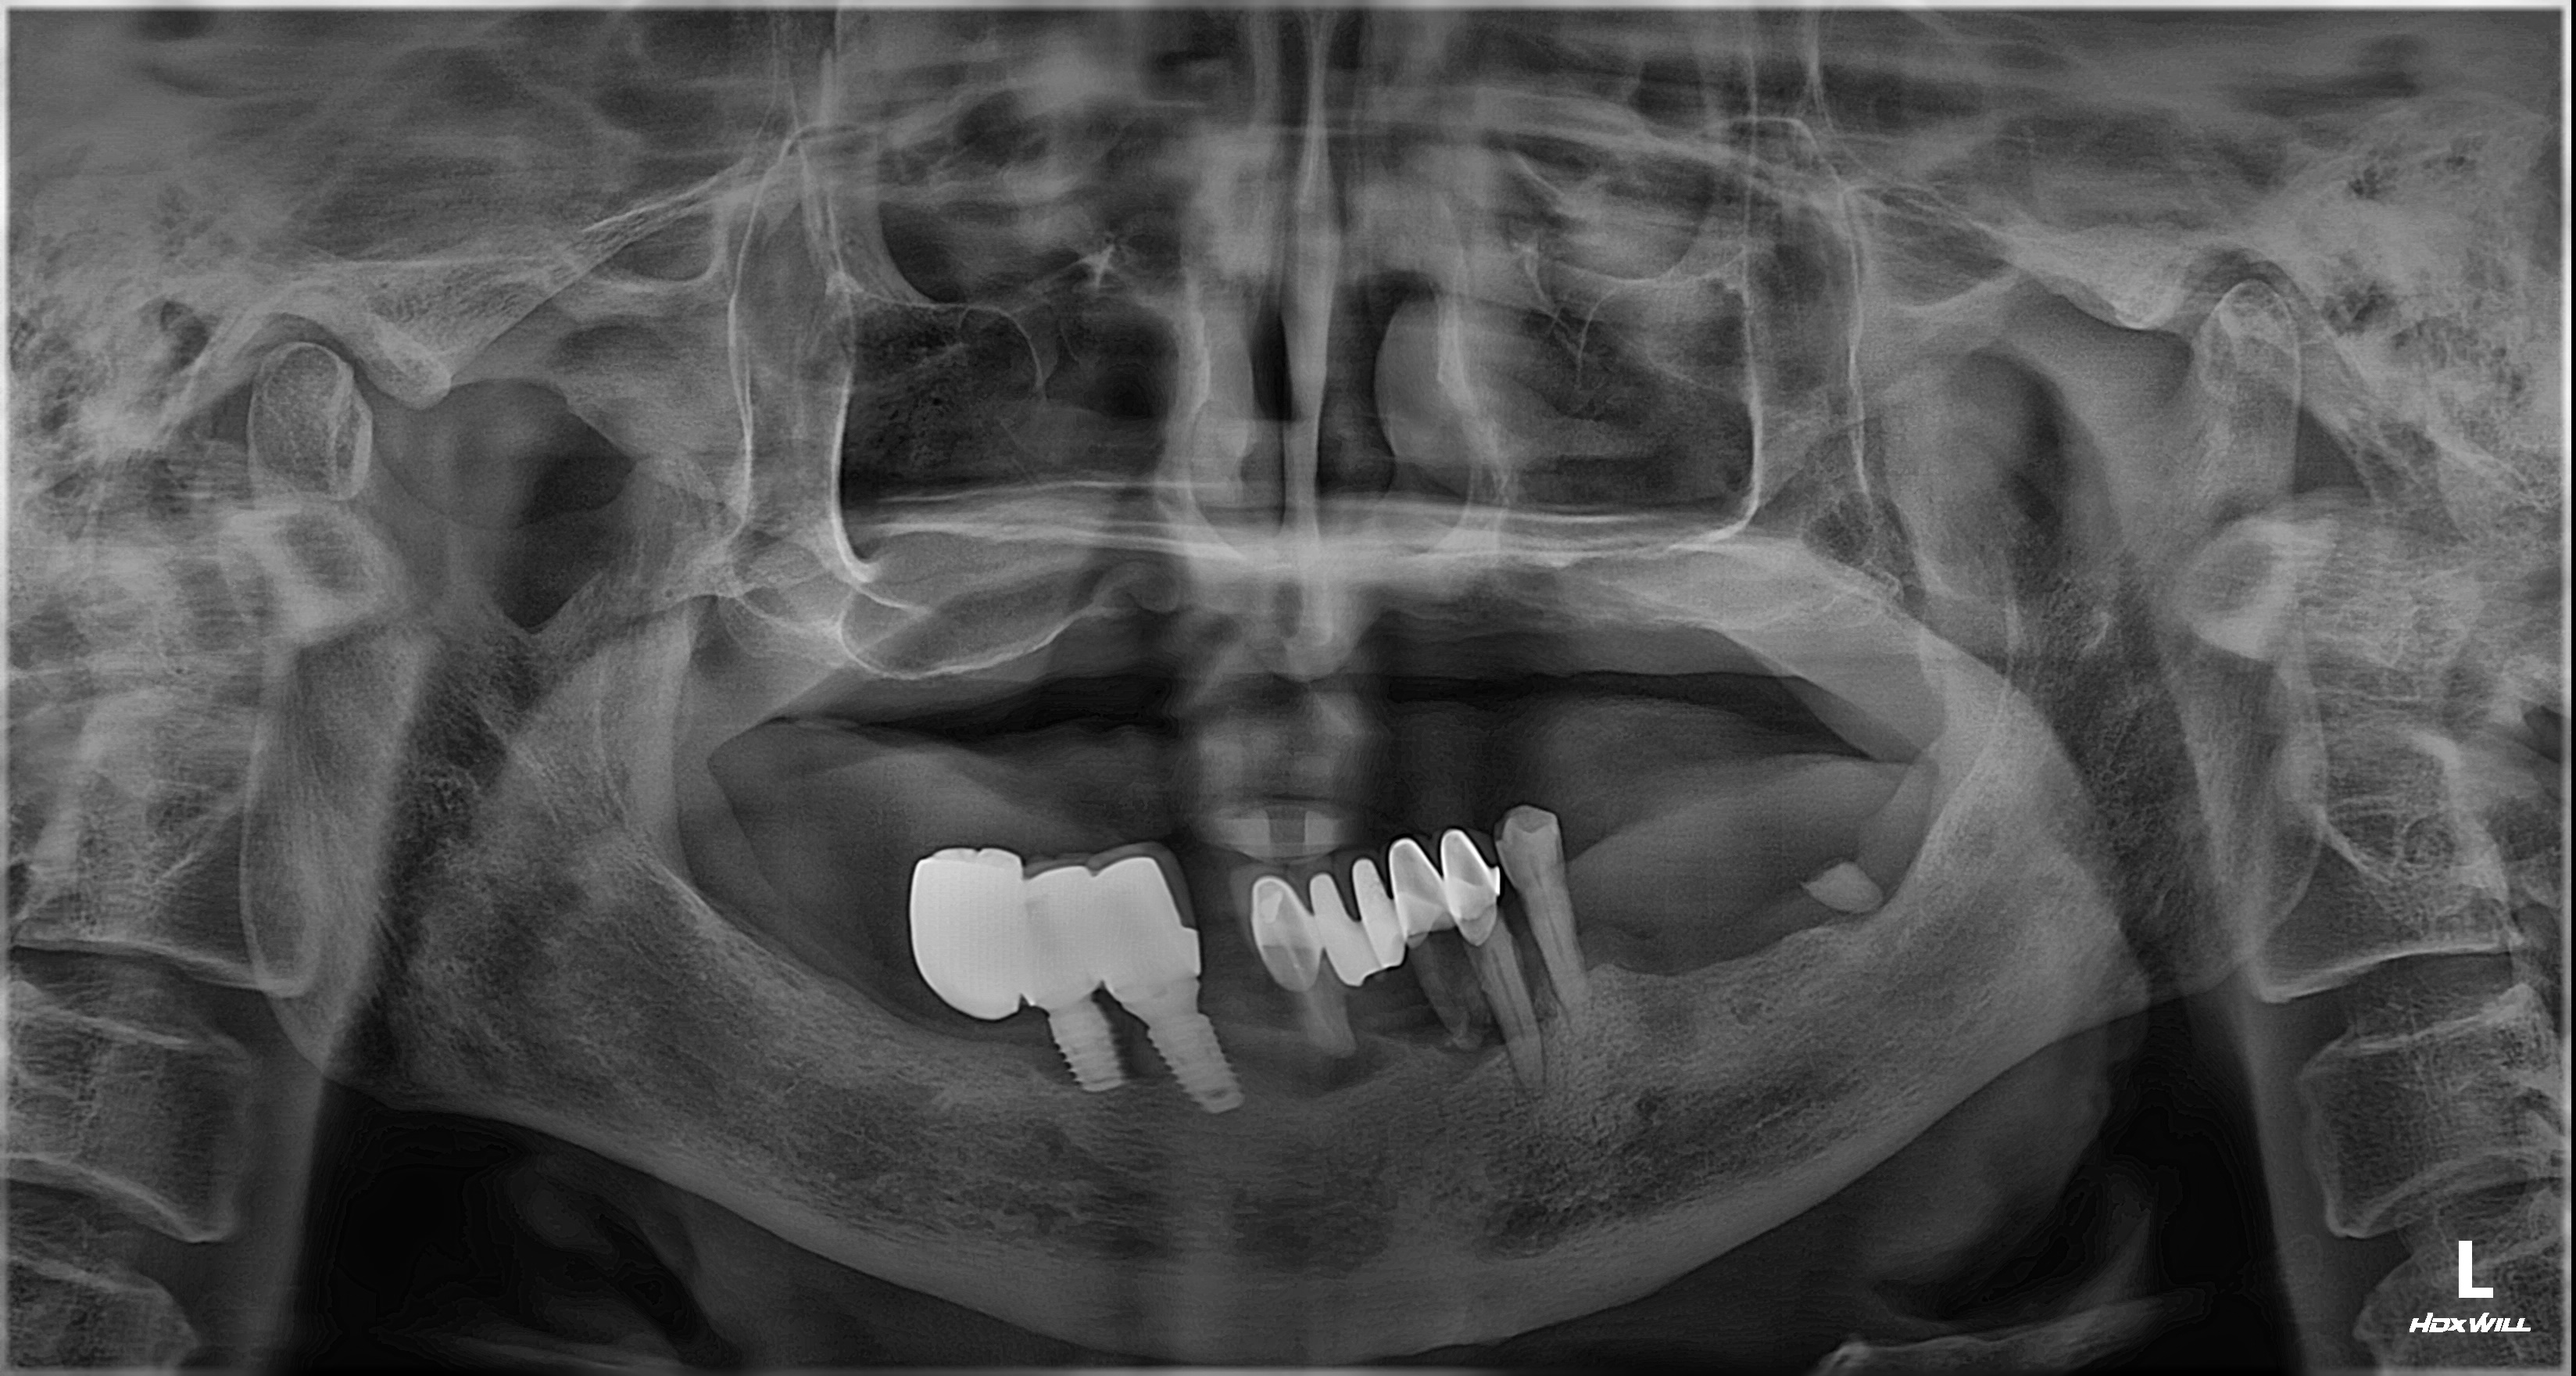

촬영일시: 2024.05.03

[ 치료기간: 2024년 05월 03일 ~2025년 03월 14일 ] ※ 365서울앞선치과의원의 모든 컬럼은 각 진료과 의료진이 직접 작성합니다. 365서울앞선치과의원 임상 케이스 게시물은 환자분께 의학적으로 정확하고 상세한 정보를 드리기 위해 각 진료과 의료진이 직접 작성하며, 모든 증례 사진은 본원 의료진이 직접 시술한 증례를 촬영한 것으로, 의료법 제23조, 제56조에 의거하며 환자분의 동의를 얻어 포스팅에 사용하였습니다. 또한 해당 케이스는 본 환자분의 치료 결과이며, 환자 상태에 따라 치료의 결과는 달라질 수 있습니다. |